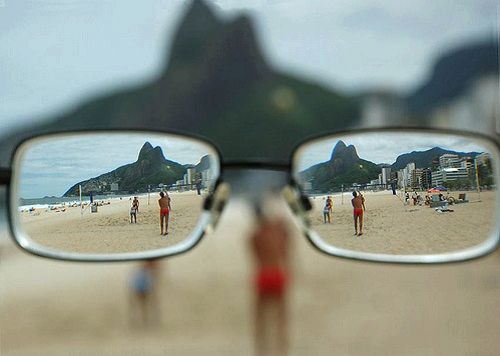

Найпростіший спосіб лікування - це призначення очок зі спеціальними лінзами. Вони мають вигляд циліндра. Це один з найпростіших методів корекції зору, але він не дає 100% позитивний ефект. Для призначення очок необхідно провести ретельну діагностику.